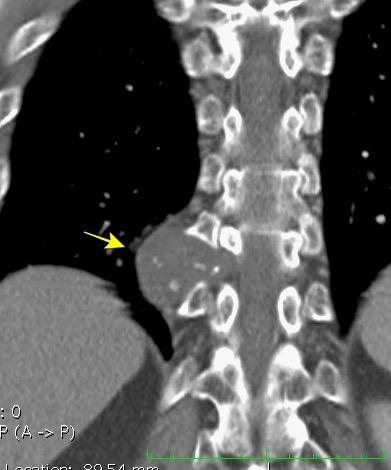

95. GANGLIOS CON CALCIO/HUESO

Preda L et al. Calcified metastatic mediastinal lymph nodes from mucinous breast adenocarcinoma.

Eur Radiol 2004/ Patel SV, et al. CT demonstration of calcified metastatic mediastinal lymph nodes. Clin Radiol 1998

Tb/ Hongos

Sarcoidosis

Silicosis Ca. de pulmón

Linfoma (post tto.)

Pneumocistis

Amiloidosis

Castleman

Metástasis: Osteosarcoma Tiroides Colon Ovario

Carcinoma mucinoso. (mama, ovario, etc.)

AdenoCa. de pulmón

0,84% en no tratados. Apter. S. AJR.2002. Ganglios tratados

En ganglios tratados

2-8% > 8 meses después.

McLennan TW et al... Radiology 1975

Bertrand M, et al. AJR 1977

Strijk SP. Acta Radiol Diagn. 1985

Linfoma de Hodgkin irradiado años antes

Tuberculosis

Metástasis de Ca. epidermoide de pulmón, ovario, seminoma, tiroides, estómago

Linfoma Tratado/Hodgkin no tratado.(21%)

Micobacteria no Tb

Sarcoidosis (raro)

Tb ganglionar

Hiperplasia nodal grasa/Whipple

Leucemia/Adenitis viral (herpes simple)

Mod. de Brant WE et al. Fundamentals of Diagnostic Radiology.2007

Hopper KD et-al. AJR 1990/ Webb WR. The Mediastinum en Thoracic Imaging.2005